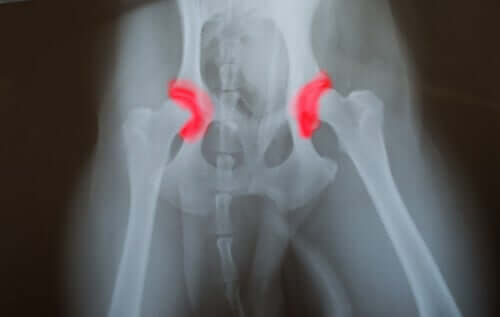

Dysplazja stawu biodrowego lub łokciowego jest chorobą dziedziczną, która przechodzi z pokolenia na pokolenie. Polega ona na tym, że kości tworzące staw biodra lub łokcia, nie są prawidłowo umieszczone lub ustawione.

Prowadzi to do tarcia i niewłaściwych ruchów, co z kolei powoduje przyspieszone zużycie stawów. A to prowadzi do innych problemów spowodowanych nieprawidłowym działaniem stawów. Problem z tą chorobą polega na tym, że rozwija się w ukrycia.